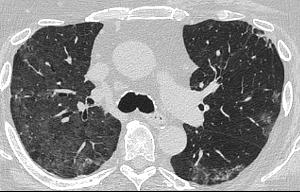

A 58-year-old female with recently diagnosed COVID-19 pneumonia was found to have a dry cough and dyspnoea in the setting of persistent bilateral hilar and mediastinal lymphadenopathy associated with bilateral nodular infiltrates. Of note, she immigrated to the USA from India 10 years prior, with the most recent travel to India 2 years ago. Quantiferon testing upon return to the USA was negative at that time. Workup included bronchoscopy with endobronchial ultrasound revealing non-caseating granulomas with negative stains for acid-fast bacilli (AFB). She was diagnosed with Stage 3 sarcoidosis and initiated on prolonged steroid taper with improvement of symptoms. With taper of steroid dose, however, she developed lymphocyte-predominant exudative effusion with negative cultures, and was reinitiated on a protracted steroid course with rapid symptom resolution. At 4-month follow-up, she had worsening CT findings upon steroid taper, and was started on azathioprine. One month later, she required hospital admission for worsening dyspnoea and fatigue. She was noted to be febrile, tachycardic, and tachypnoeic with worsening

hypoxia. Subsequent CT chest showed progression of bilateral nodular infiltrates with new right upper lobe consolidation and air bronchograms concerning for multifocal pneumonia (Figure 1). Incidentally, she was also noted to have calcified splenic granulomas. She developed rapid clinical deterioration, ultimately requiring mechanical ventilation, pressor support, and continuous renal replacement therapy. Repeat bronchoscopy revealed diffuse alveolar haemorrhage with multiple AFB smears positive for Mycobacterium tuberculosis. She was immediately initiated on quadruple therapy, but unfortunately, despite treatment, developed refractory shock and passed away 2 weeks after initial presentation.

A) Initial adenopathy with peripheral patchy ground glass opacities in the right lung following COVID-19 pneumonia. B) Persistent bulky adenopathy 1 year after initial presentation. C) Extensive nodularity throughout the right lung with increasing confluent opacities in the right upper lobe and stable mediastinal lymphadenopathy 2 years after initial presentation. D) Tuberculosis superimposed on sarcoidosis with progression of nodular infiltrates, worsening right upper lobe consolidation, and air bronchograms with incidental calcified splenic granulomas (not pictured).

Figure 1: CT progression of patient’s sarcoidosis and tuberculosis.